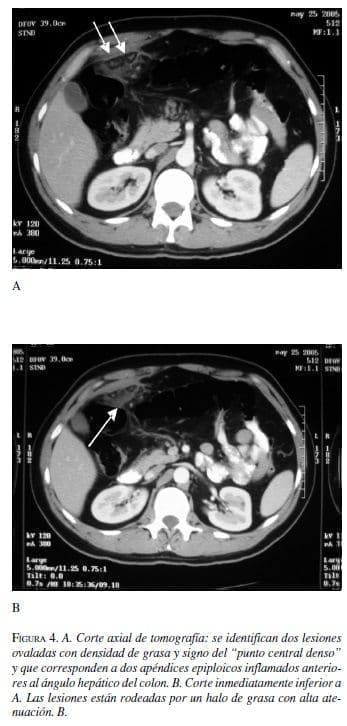

Hombre de 43 años quien consulta por 4 días de dolor en el hipocondrio derecho acompañado de malestar general y náuseas. Velocidad de sedimentación aumentada y leucocitosis leve. Se le ordena tomografía contrastada de abdomen con sospecha de absceso hepático.

Los apéndices epiploicos son normalmente invisibles en la tomografía a menos que estén rodeados por ascitis. Los hallazgos característicos de apendicitis epiploica son: una masa oval paracolónica con densidad de grasa que representa el apéndice inflamado o infartado, con aumento en la atenuación de la grasa a su alrededor, un anillo hiperatenuante bien definido que rodea a la masa que representa al peritoneo visceral inflamado y en algunas ocasiones un “punto” central de alta atenuación que representa los vasos ingurgitados o trombosados o áreas centrales de hemorragia (3, 8-9).

Ocasionalmente la pared del colon se encuentra engrosada, así como el peritoneo parietal adyacente (7). Los diagnósticos diferenciales son diverticulitis, infarto del omento (epiplón mayor) y apendicitis. Realizar un diagnóstico correcto es importante ya que la apendicitis epiploica y el infarto del omento son condiciones típicamente autolimitadas, mientras que la apendicitis aguda y en muchos casos la diverticulitis requieren cirugía u otra intervención (3).